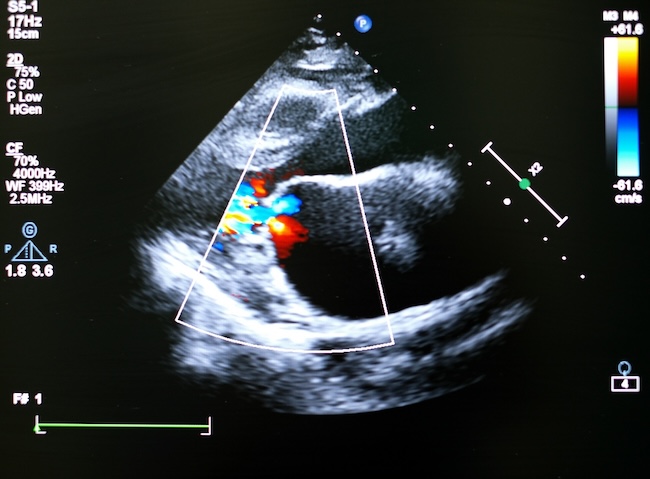

Transcatheter aortic valve implantation (TAVI) merupakan prosedur jantung minimal invasif untuk menggantikan katup aorta pada pasien dengan stenosis aorta berat tanpa memerlukan pembedahan jantung terbuka. TAVI telah menjadi terapi standar berbasis bukti yang secara signifikan memperbaiki prognosis pasien stenosis aorta. Berbeda dengan dahulu di mana surgical aortic valve replacement (SAVR) menjadi pilihan terapi.[1,2]

Keberhasilan prosedur TAVI sangat bergantung pada kemajuan teknik implantasi dan perencanaan prosedural. Akses transfemoral saat ini menjadi pilihan karena bersifat paling minimal invasif dan berhubungan dengan luaran klinis yang lebih baik dibandingkan akses lainnya. Pemanfaatan pencitraan berperan penting dalam evaluasi anatomi, pemilihan ukuran katup, serta penurunan risiko komplikasi.

Risiko komplikasi tindakan TAVI mencakup gangguan sistem konduksi, kebocoran paravalvular, komplikasi vaskular, dan kejadian serebrovaskular. Oleh karena itu, identifikasi faktor risiko, pemahaman mekanisme komplikasi, serta penerapan strategi pencegahan dan penanganan yang tepat menjadi penting.